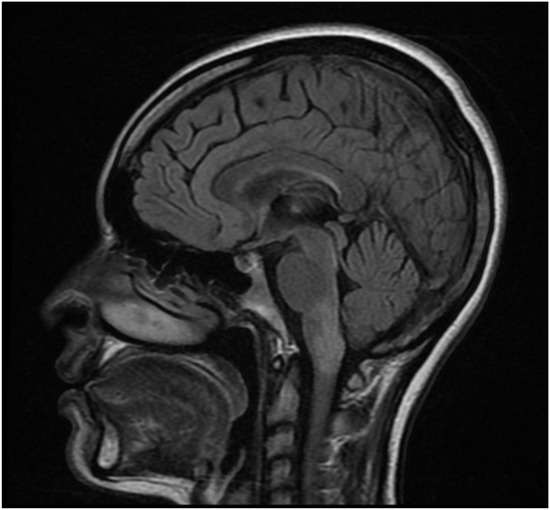

Background: Neuromyelitis optica spectrum disorder (NMOSD) is an autoimmune demyelinating disease with important disability accumulation. Early-onset NMOSD, defined as disease onset before age 50, exhibits distinct clinical characteristics compared to late-onset disease. We present a case series of patients with first symptom onset

Background: Neuromyelitis optica spectrum disorder (NMOSD) is an autoimmune demyelinating disease with important disability accumulation. Early-onset NMOSD, defined as disease onset before age 50, exhibits distinct clinical characteristics compared to late-onset disease. We present a case series of patients with first symptom onset before age 30. Methods: A retrospective review of 10 patients diagnosed with NMOSD at our center in San Luis Potosí, Mexico, with disease onset before age 30. Clinical presentation, imaging findings, AQP4 antibody status, treatment response, and disability outcomes were analyzed. Results: The mean age at onset was 18.6 years (range 6–30). Area postrema syndrome was the most common presentation (40%), followed by acute myelitis and optic neuritis (30% each). All tested patients were AQP4-positive. The mean EDSS at follow-up was 6.6, indicating severe disability. Most patients received rituximab with variable response rates. Conclusions: Our cohort showed higher disability than reported in other early-onset series, emphasizing the need for prompt diagnosis and aggressive treatment in this population.

Figure 1